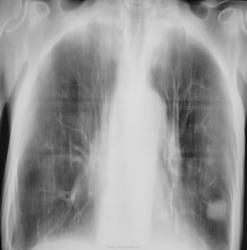

Для ТВС низко (где Nikolas?), МТS , гамартома?

в пользу туберкулем говорит многочисленный туберкулезный архив.И мысли мои за них. Но это может ввести врача в опасное для пациента заблуждение и к потере времени. Посттуберкулезные рубцы - ложе рака. Надо ставить два диагноза: туберкулёма, рак. Срочно бронхоскопия с пункционной биопсией. Эти манипуляции у нас в стране выполнялись 40 лет назад. Многое зависило от бронхолога и очень от класса морфологов. Последние, при высокой квалификации, дают положительный результат в 75%.

Узловое образование с зубчатыми передними контурами. Не исключается версия приферичесого рака лёгкого. Показана РКТ, ну и ФЛО-архив посмотреть неплохо бы.

в пользу туберкулем говорит многочисленный туберкулезный архив.И мысли мои за них. Но это может ввести врача в опасное для пациента заблуждение и к потере времени. Посттуберкулезные рубцы - ложе рака. Надо ставить два диагноза: тберкулема, рак. Срочно бронхоскопия с пункционной биопсией. Эти манипуляции у нас в стране выполнялись 40 лет назад. Многое зависило от бронхолога и очень от класса морфологов. Последние при высокой квалификации дают положительный результат в 75%.

Мне кажется, что для бронхоскопии эта тень достаточно далеко, за субсегментами. А пункционную биопсию не все эндоскописты могут сделать-и технически, и морально.

По характеру контура тени, больше данных за перефирический рак. + рисунок диффузно усилен. Может пациент курильщик и развился у него тот самый "никотиновый" рак.

На томограммах лучше видно рак лёгкого.

Пациента взяли себе онкологи.